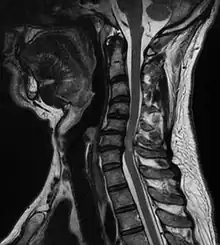

Compression médullaire

Une compression médullaire peut être décrite comme une déformation de la moelle spinale due à un hématome, une tumeur ou une simple hernie discale.